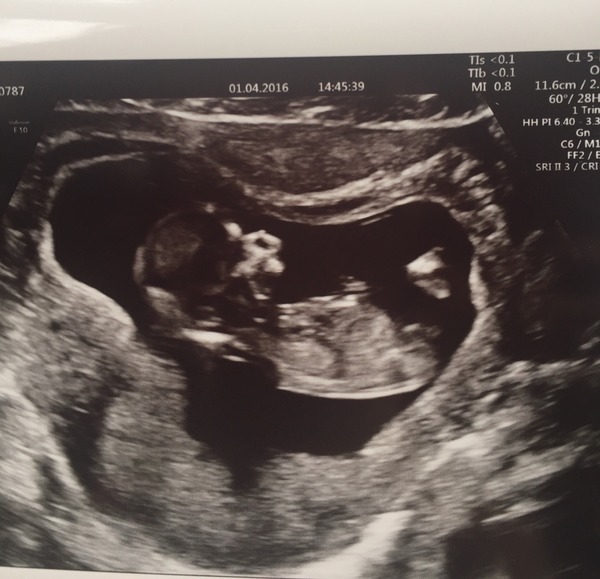

I have my gender scan tomorrow..I am SO excited!! I keep swaying between what 'vibe' I am getting, pink or blue I'm just happy if baby is healthy.

If anyone fancies a guess go ahead, I'll attach my 12 week scan Grin

indi im pretty poor at the whole scan guessing but when I looked I thought girl first so I'll go team pink. Fingers crossed baby plays ball and is lying in a good position for you x